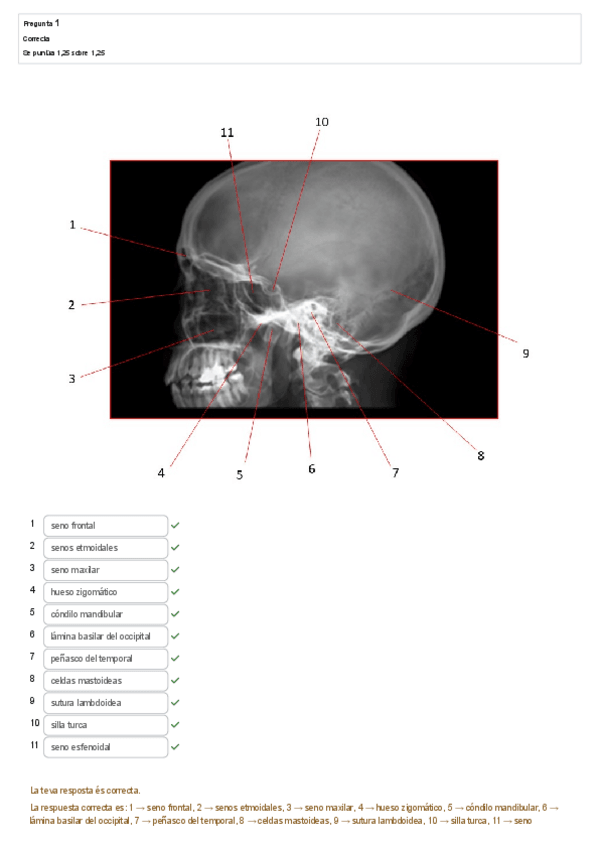

He publicado nuevos test de 1º Aparato Locomotor: CUESTIONARIO-CRANEO.pdf

8 páginas